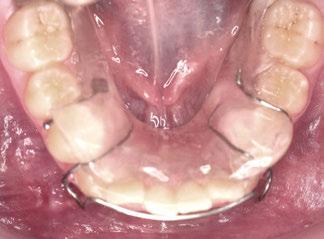

Tras la terminación de la fase ortopédica, se continuó con la colocación de los brackets

mencionados anteriormente. La prescripción de estos fue de alto torque en los incisivos superiores y en los cuatro caninos, y de bajo en los incisivos inferiores. Tras 12 meses desde la colocación de los brackets y una vez conseguida la normalización de las relaciones oclusales, se colocaron unos retenedores fijos de canino a canino en ambas arcadas de acero trenzado de 6 hilos (.017” superior y .019” inferior) y un guarda de contención nocturna hasta la terminación del crecimiento puberal.

Los retenedores fijos (13, 14) FLAS y FLAI (férula lingual anterosuperior e anteroinferior, respectivamente) de alambre de acero trenzado de 6 hilos, cementados de canino a canino, aportan estabilidad a los sectores anteriores, y el splint o guarda como aparato de contención nocturna hasta la terminación del crecimiento puberal, aporta estabilidad a los resultados conseguidos.